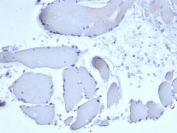

Negative control: IHC staining of FFPE human skeletal muscle with recombinant Mammaglobin A antibody (rMGB/6619) at 2ug/ml in PBS for 30min RT. HIER: boil tissue sections in pH 9 10mM Tris with 1mM EDTA for 20 min and allow to cool before testing.